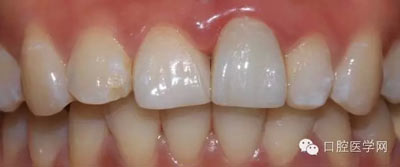

5、3MU200樹(shù)脂粘接劑粘固全瓷冠術(shù)后照

6、術(shù)后一周照,牙齦恢復(fù)良好